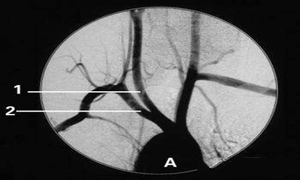

中风与西医急性脑血管病相近,临床可作脑脊液、眼底及CT、MRI等检查。短暂性脑缺血发作检查无明显异常。局限性脑梗死,患者脑脊液压力不高,常见在正常范围,蛋白质含量可高。头颅CT和MRI可显示梗死区。出血性中风在起病后1周CT能正确诊断大脑内直径在1厘米或更大的血肿。对于脑干内小的血肿或血块已变为和脑组织等密度时,MRI的诊断比CT可靠。原发性蛛网膜下腔出血主要原因为动脉瘤破裂和动静脉血管畸形,早期CT扫描,可显示破裂附近脑池或脑裂内有无凝血块,脑内或硬膜下血肿及是否合并脑出血。MRI对原发性蛛网膜下腔出血的诊断并不可靠,无CT条件下,可谨慎进行脑脊液检查。